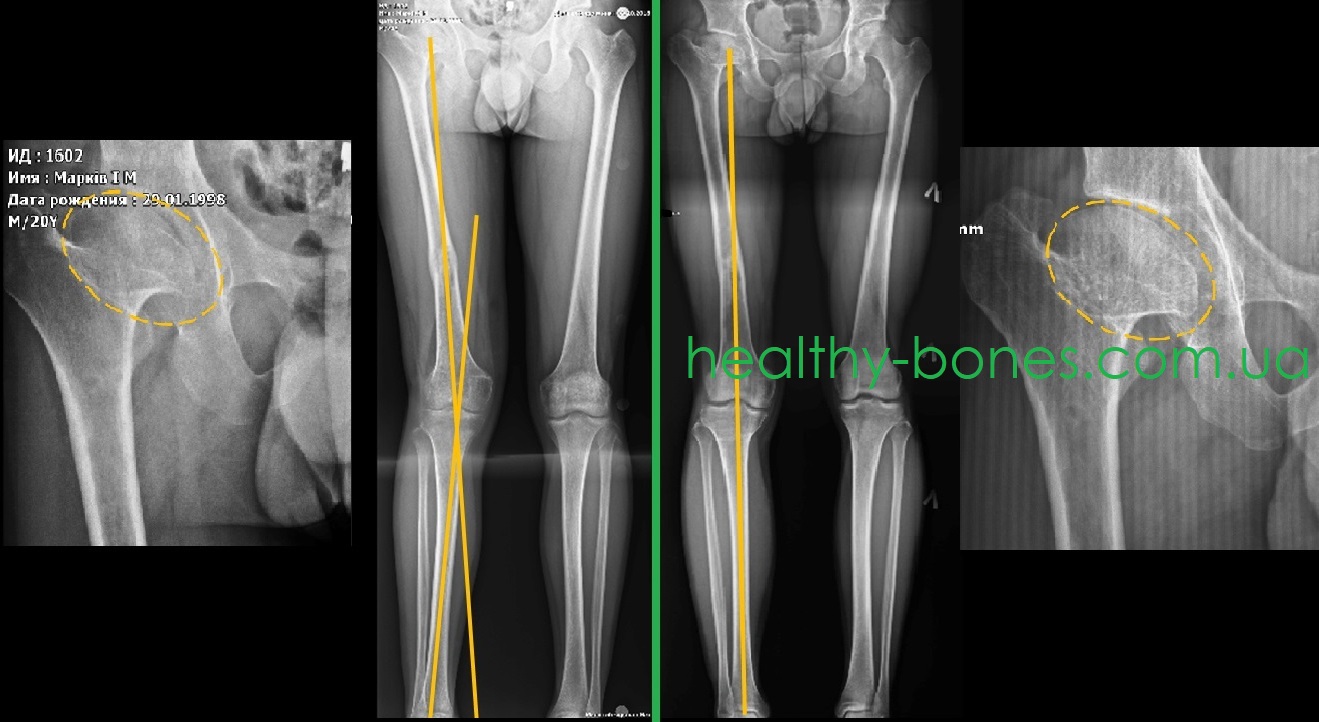

Пациент обратился к нам с жалобами на боли в области правого тазобедренного сустава и выраженную хромоту на правую ногу. В анамнезе у пациента  дисплазия правого тазобедренного сустава. В 18-ти летнем возрасте ему было предложено выполнить протезирование правого тазобедренного сустава. Но в день, когда была запланирована операция, врач порекомендовал не делать замену сустава, а поискать альтернативные способы лечения (рекомендация достойная уважения). При обследовании нами было выявлено: 1) значительное укорочение шейки правой бедренной кости с грибовидной деформацией головки, шеечно-диафизарный угол в пределах 130°; укорочение правой нижней конечности до 5 см; вальгусная деформация голени.

Нами было выполнено этапное оперативное лечение – на первом этапе выполнено удлинение правой бедренной кости, а на втором – устранена вальгусная деформация голени. Данные операции позволили максимально возможно восстановить осевую нагрузку правой нижней конечности, что позволило устранить болевой синдром в области правого тазобедренного сустава. Наряду с этим через два года после завершения лечения головка бедренной кости стала более округлой, что способствовало увеличению объема движений в суставе.

В настоящее время (два года после завершения лечения) пациент ходит без хромоты, боли в области правого тазобедренного сустава отсутствуют, он ощущает себя полноценным человеком. Работает официантом и практически весь день проводит на ногах.